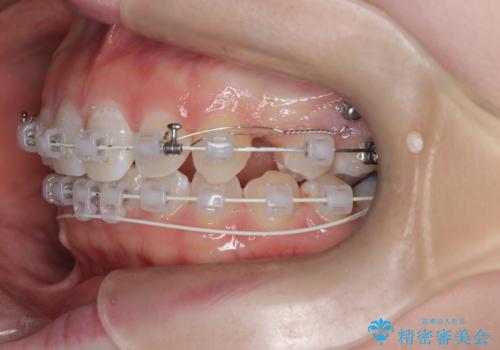

- 右上の八重歯と歯のデコボコ、そして上下の歯の中心(正中)のズレを気にされて来院されました。精密な検査の結果、歯が並ぶスペースが不足しているため、上顎の小臼歯(前から数えて4番目の歯)を抜歯し、そのスペースを利用して歯並び全体を整える治療計画を立案しました。これにより、八重歯の位置を適切に改善し、叢生(歯のデコボコ)を解消するとともに、上下の正中線のズレも改善することを目指します。

今回の矯正治療では、歯が並ぶスペースを確保するため、上顎の小臼歯を抜歯しました。抜歯によってできたスペースを有効活用し、ワイヤーやブラケットを使って右上の八重歯を適切な位置へ移動させ、叢生を解消していきました。また、治療を通じて上下の歯の中心である正中線のズレも改善するよう、慎重に歯を動かしました。治療の結果、長年気にされていた八重歯と歯のデコボコが解消され、上下の正中線も一致。機能的にも審美的にもバランスの取れた、美しい歯並びと笑顔を獲得していただけました。